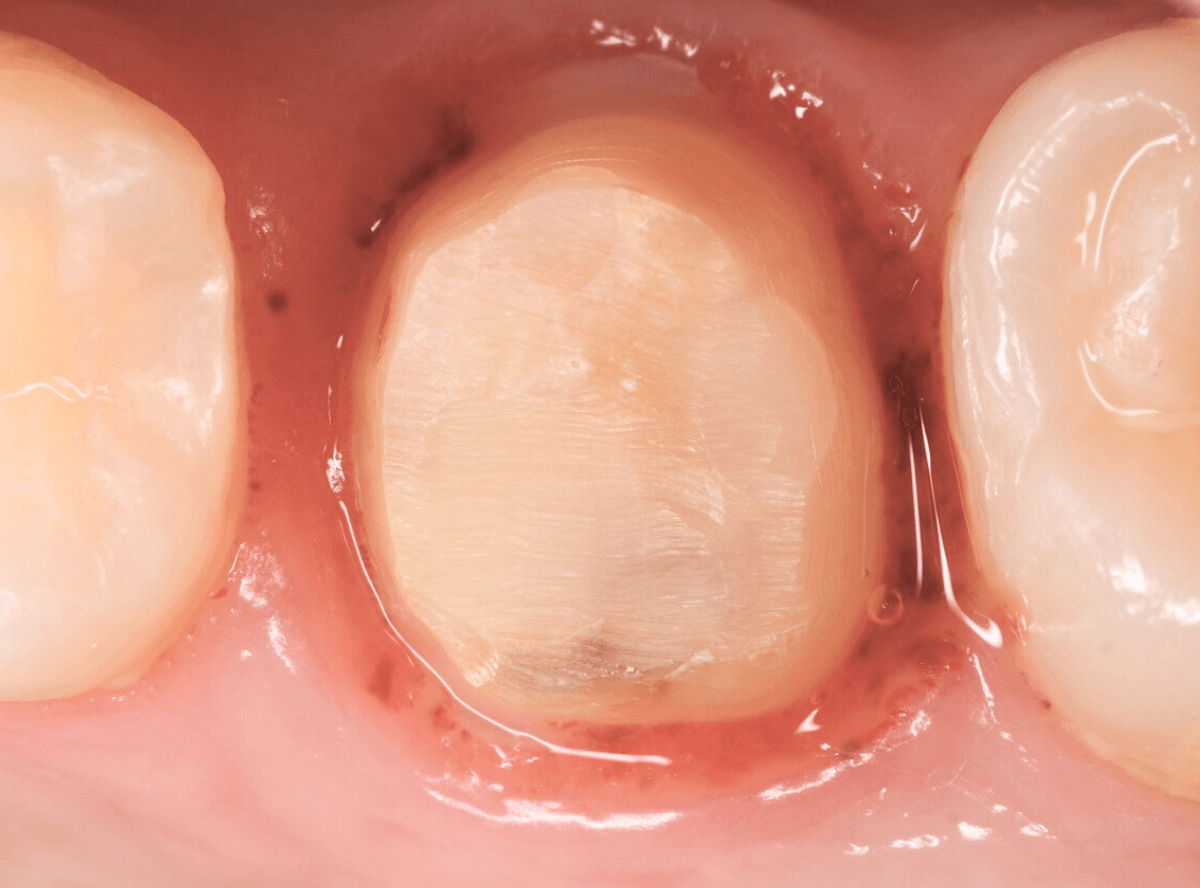

保険診療で行うさし歯「レジン前装冠」が入っています。

「レジン前装冠」は裏から撮影した写真を見ていただければわかるように、銀歯の上にレジン(プラスチック)を盛ったさし歯で、実質的には銀歯です。

銀歯の上にプラスチックを盛るために、歯をかなり大きく削る必要があったり、短期間で劣化・変色する(この方の差し歯も劣化してのっぺりした黄土色になっています)、金属の色素が歯肉に溶け出して歯肉が黒くなる(メタル・タトゥー)などのデメリットがあります。